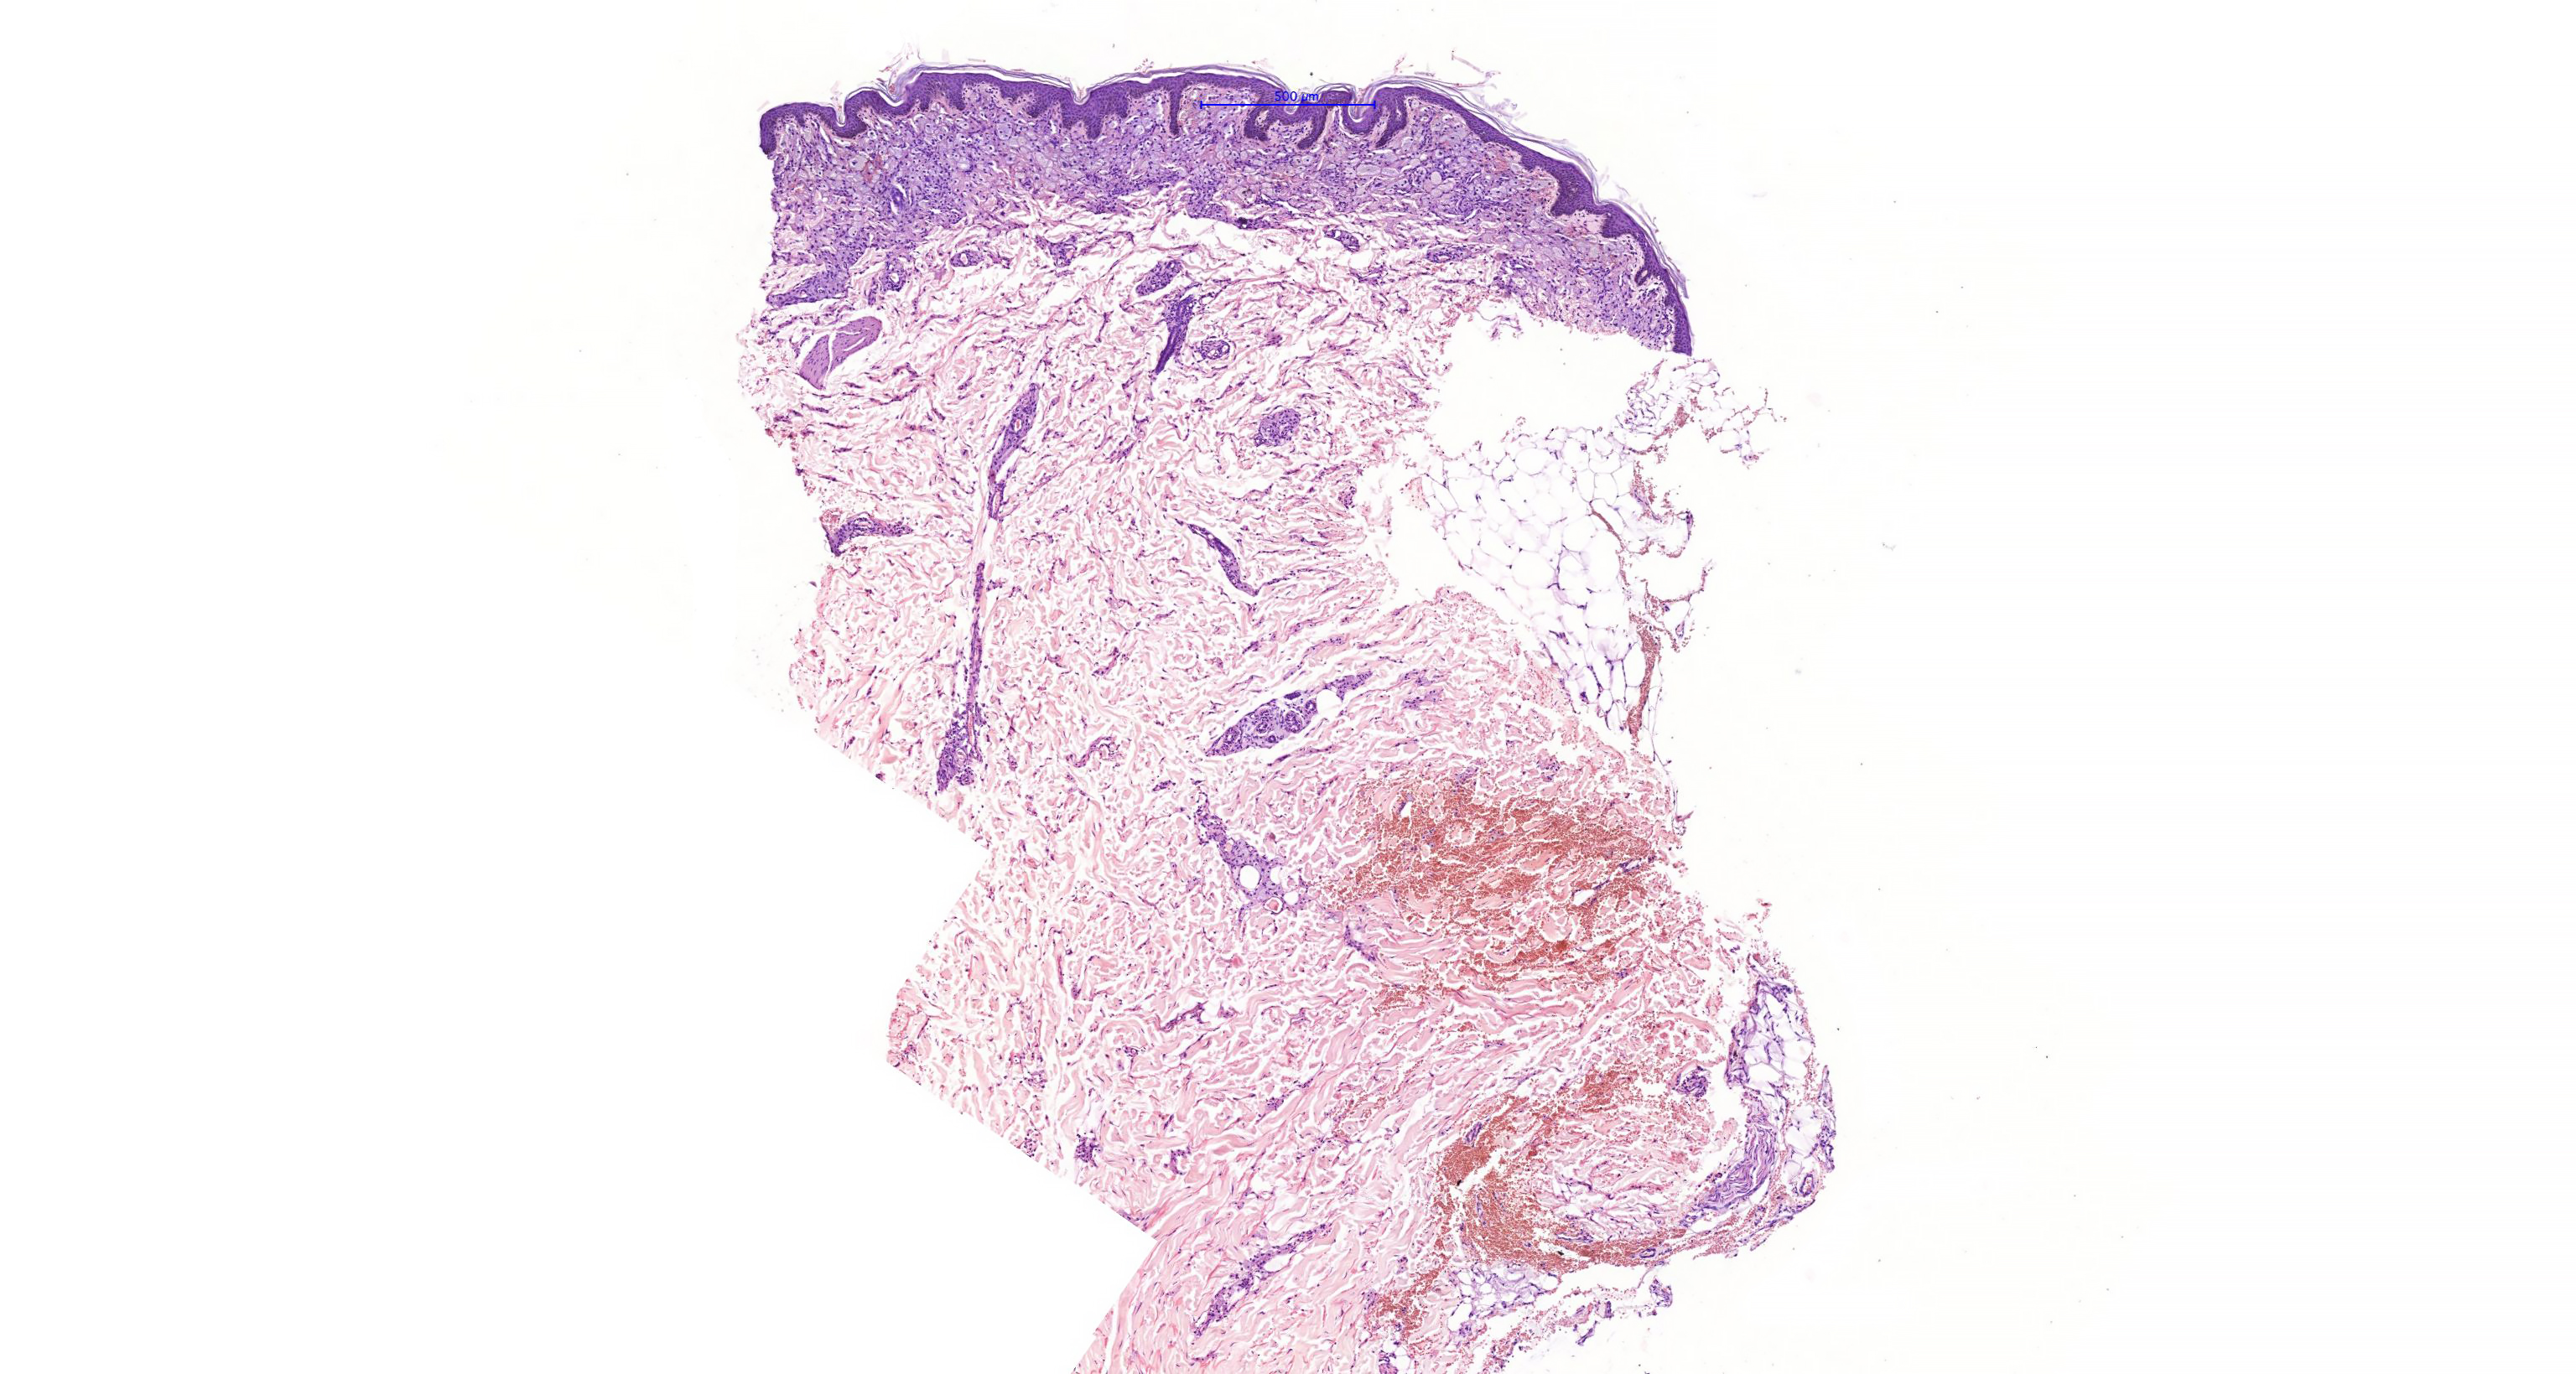

From www.researchgate.net